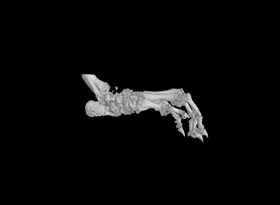

1.掃描重構(gòu):常規(guī)樣本,一個視野可以掃的樣本,按以上報價。對于一些特殊樣本或較大樣本,可能需要多個視野掃,費用按相應(yīng)的視野數(shù)計算,比如大鼠爪子至少需要3個視野。